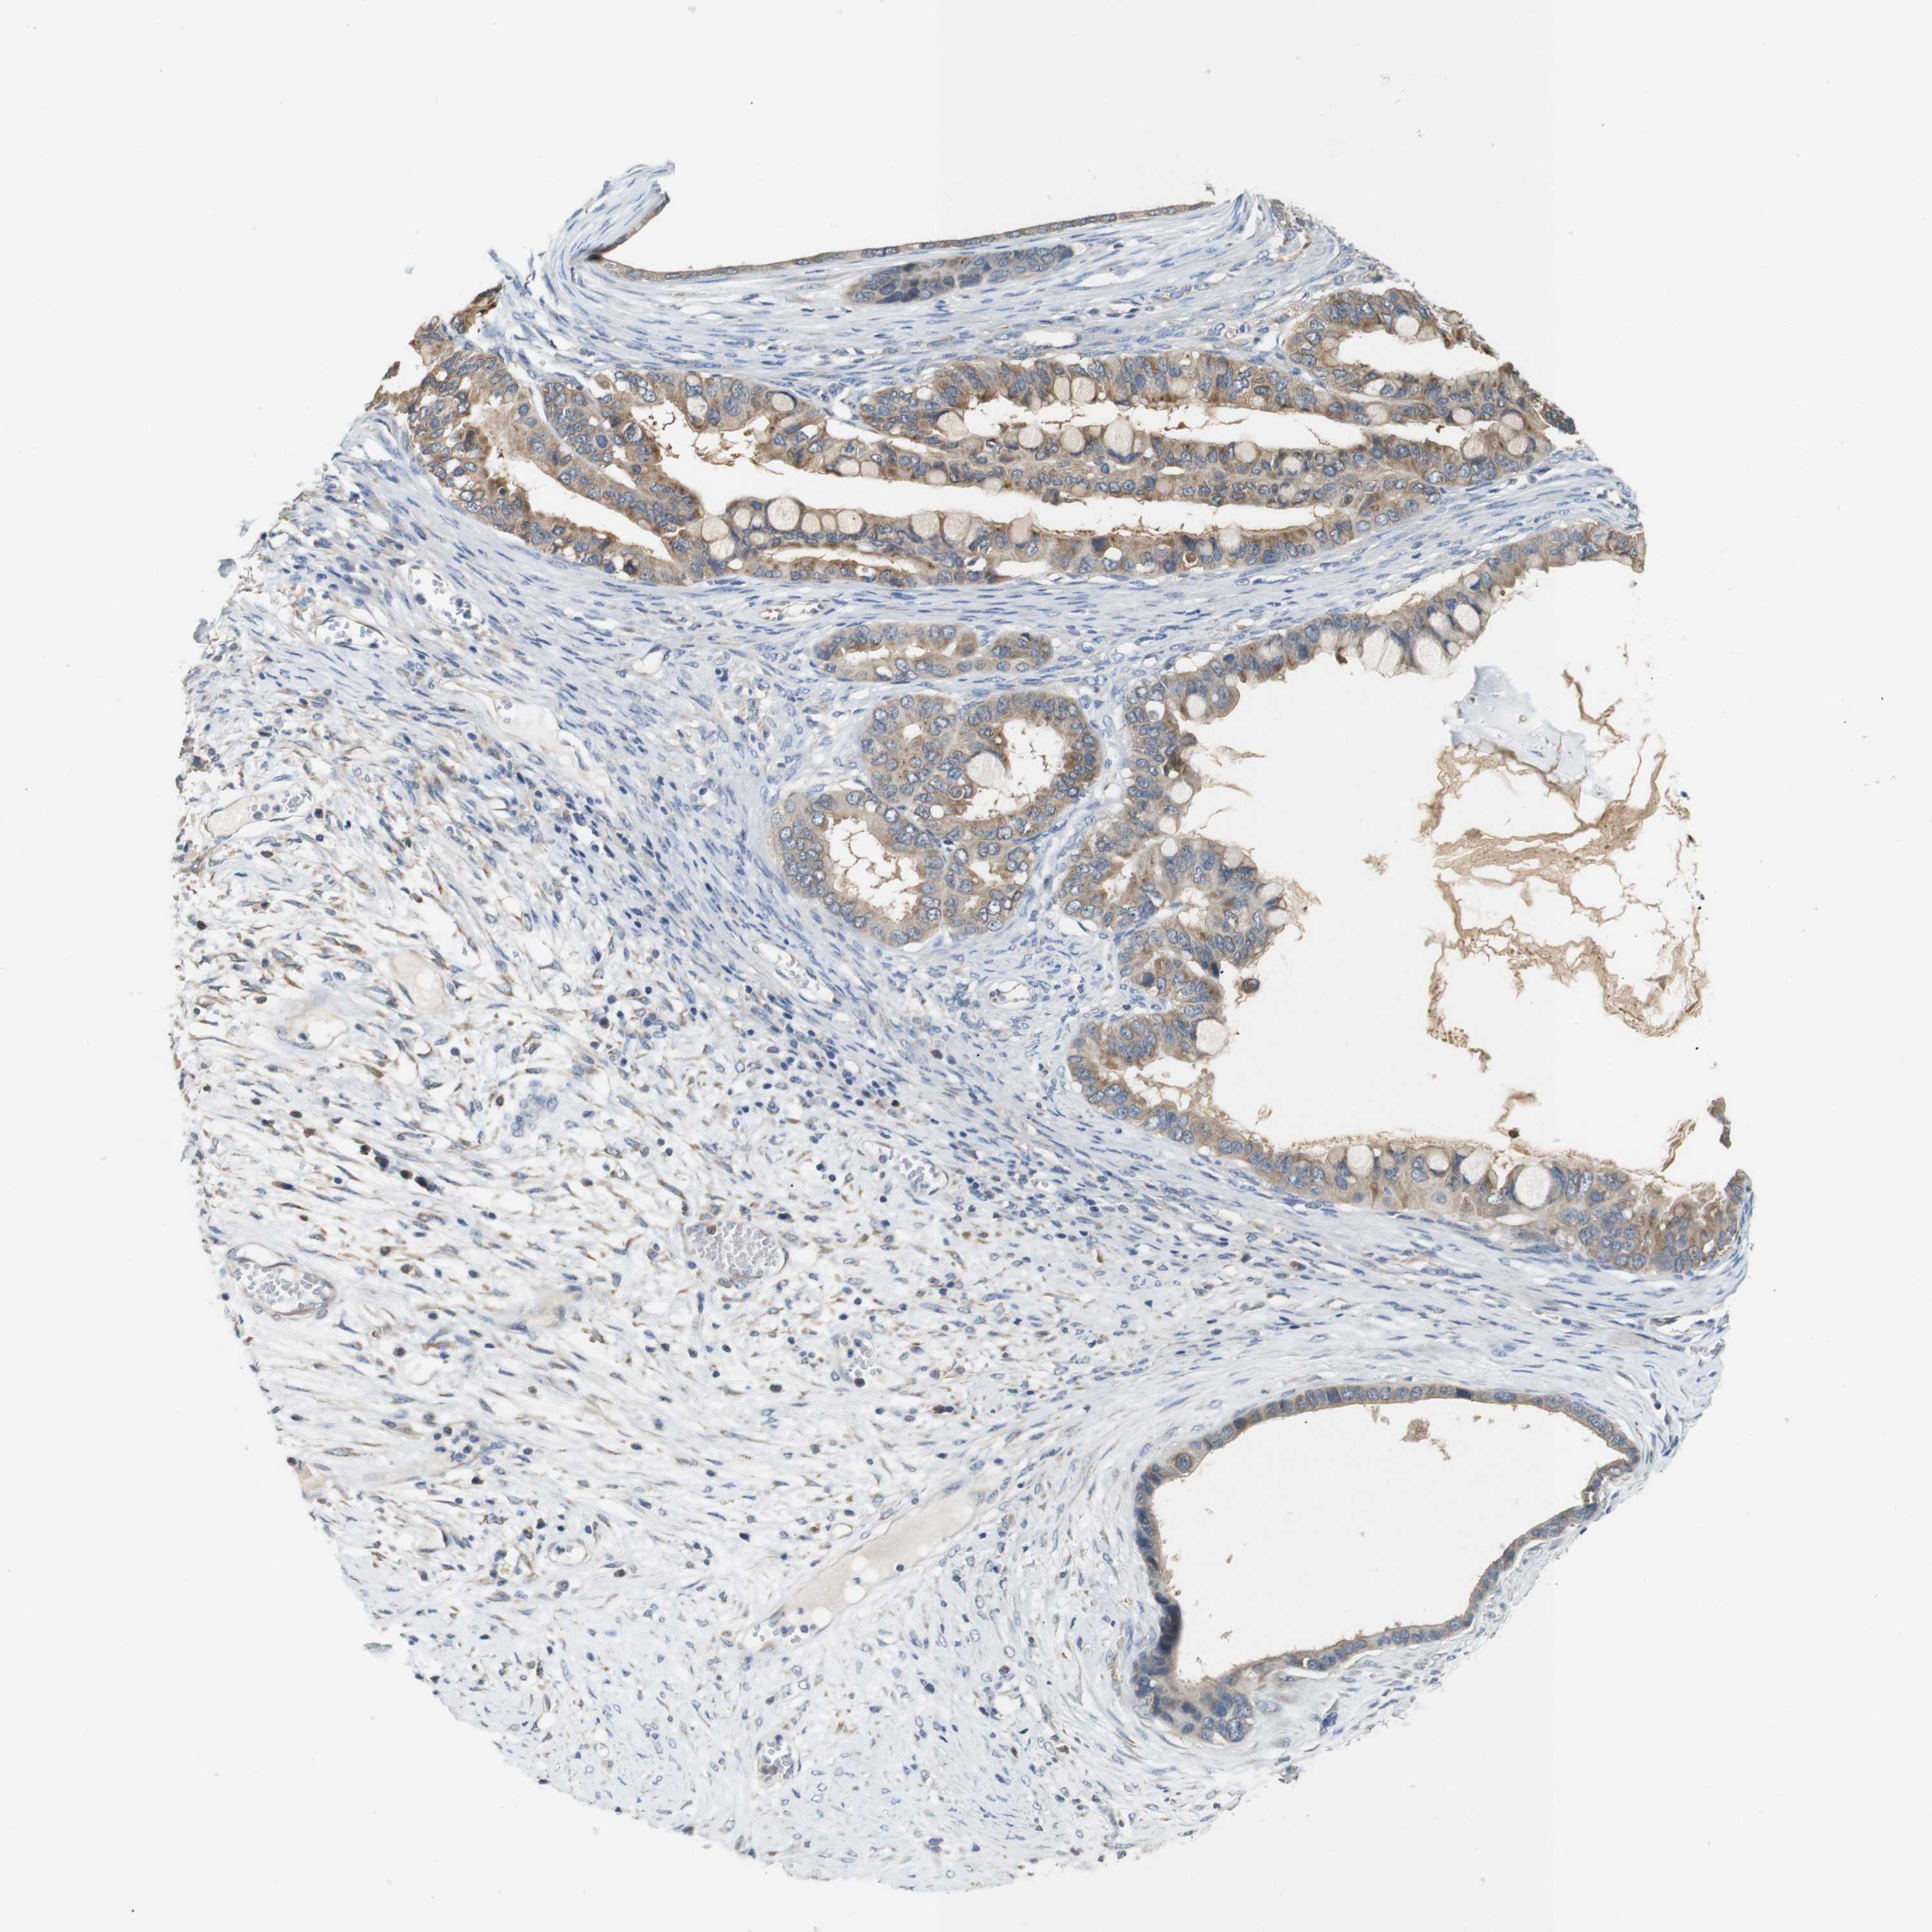

OVARIAN CANCER - Protein expressioni

A mouse-over function shows sample information and annotation data. Click on an image to view it in a full screen mode. Samples can be filtered based on level of antibody staining by selecting one or several of the following categories: high, medium, low and not detected. The assay and annotation is described here.

Note that samples used for immunohistochemistry by the Human Protein Atlas do not correspond to samples in the TCGA dataset.

Antibody stainingi

Antibody staining in the annotated cell types in the current human tissue is reported as not detected, low, medium, or high, based on conventional immunohistochemistry profiling in selected tissues. This score is based on the combination of the staining intensity and fraction of stained cells.

Each image is clickable and will lead to virtual microscopy that enables deeper exploration of all samples and also displays staining intensity scores, fraction scores and subcellular localization as well as patient and tissue information for each sample.

Antibody HPA013994

Antibody HPA013995

Cystadenocarcinoma, serous, NOS

Carcinoma, endometroid

Cystadenocarcinoma, mucinous, NOS

Carcinoma, NOS